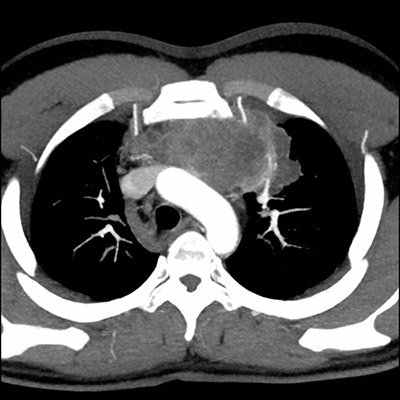

Здесь представлены компьютерно-томографические срезы на разных уровнях. Мы имеем возможность видеть просветы всех бронхов, оценить состояние их стенок и окружающей легочной паренхимы. Для того чтобы лучше оценить характер патологических изменений, возможно использование КТ высокого разрешения.

КТ средостения

Компьютерная томография средостения — это рентгенологическое исследование мягких тканей в области грудной клетки при помощи томографа. Процедура позволяет сделать четкие снимки исследуемой зоны и создавать трехмерную модель органов.

Что показывает КТ средостения

Компьютерная томография дает подробную информацию о состоянии всех тканей, костей и органов в грудной области. Чувствительная методика позволяет определить наличие заболеваний на любом этапе их развития, в том числе и на запущенных стадиях. Особенно полезна процедура в случаях, когда есть подозрение на наличие опухолейлегких, рака костей или туберкулеза, а также других опасных болезней органов грудной клетки.

КТ органов грудной клетки (воспалительные заболевания, опухоли верхних и нижних дыхательных путей на самой ранней стадии заболевания, травмы: повреждения бронхов, травмы грудной клетки)

КТ органов грудной клетки — информативный вид диагностики заболевания сердца, легких, органов средостения, пищевода, лимфатических узлов, мягких тканей. В 40 % случаев КТ позволяет получить информацию, которая обычным рентгенологическим методам не доступна.